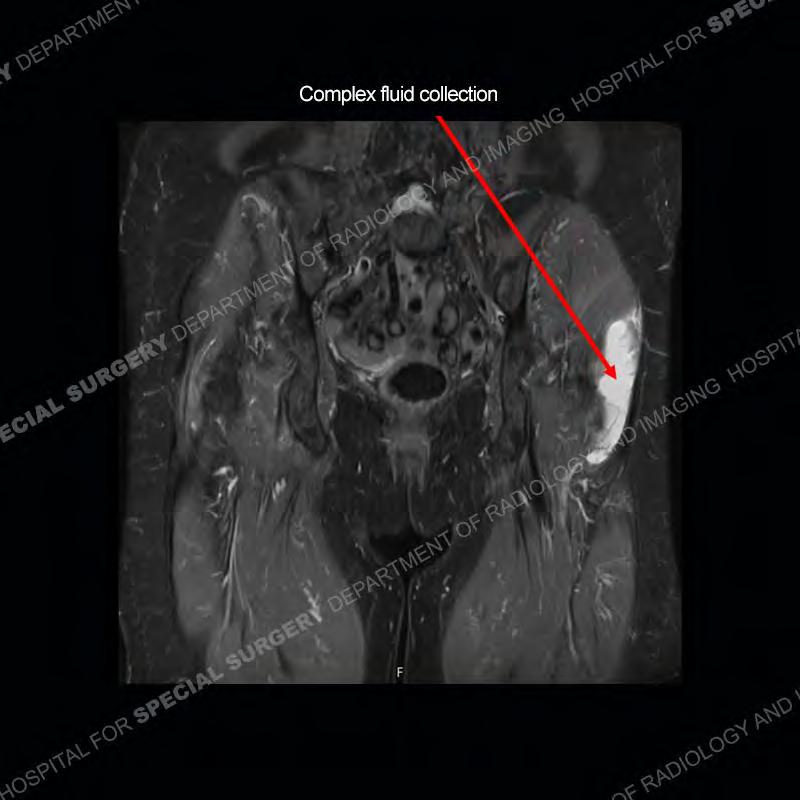

The radiograph is not particularly contributory in this case. The MRI demonstrates markedly abnormal architecture of the gluteus minimus and anterolateral band of the gluteus medius. Portions of the tendons are high signal, portions are highly attenuated, and portions are disrupted. A large, complex fluid collection is present in the adjacent soft tissue.

Diagnosis: Gluteal Tendinosis and Disruption with Complex Trochanteric Bursal Collection

The bursae about the greater trochanter can be a little bit confusing especially given the terminology. Trochanteric bursitis is implied to mean the subgluteus maximus bursa which is present deep to the maximus and just lateral/superficial to the trochanter. That is the bursa involved in this case. In this case the complexity of the bursa relates to the tendon tearing with inflammatory change and probably hemorrhage accounting for the complexity. Two other, less frequently involved bursa are also present. The subgluteus medius and subgluteus minimus bursa are found just deep to the named tendons. Although pathology does frequently follow the previously described pattern it is possible to have isolated pathology to either the medius or minimus.